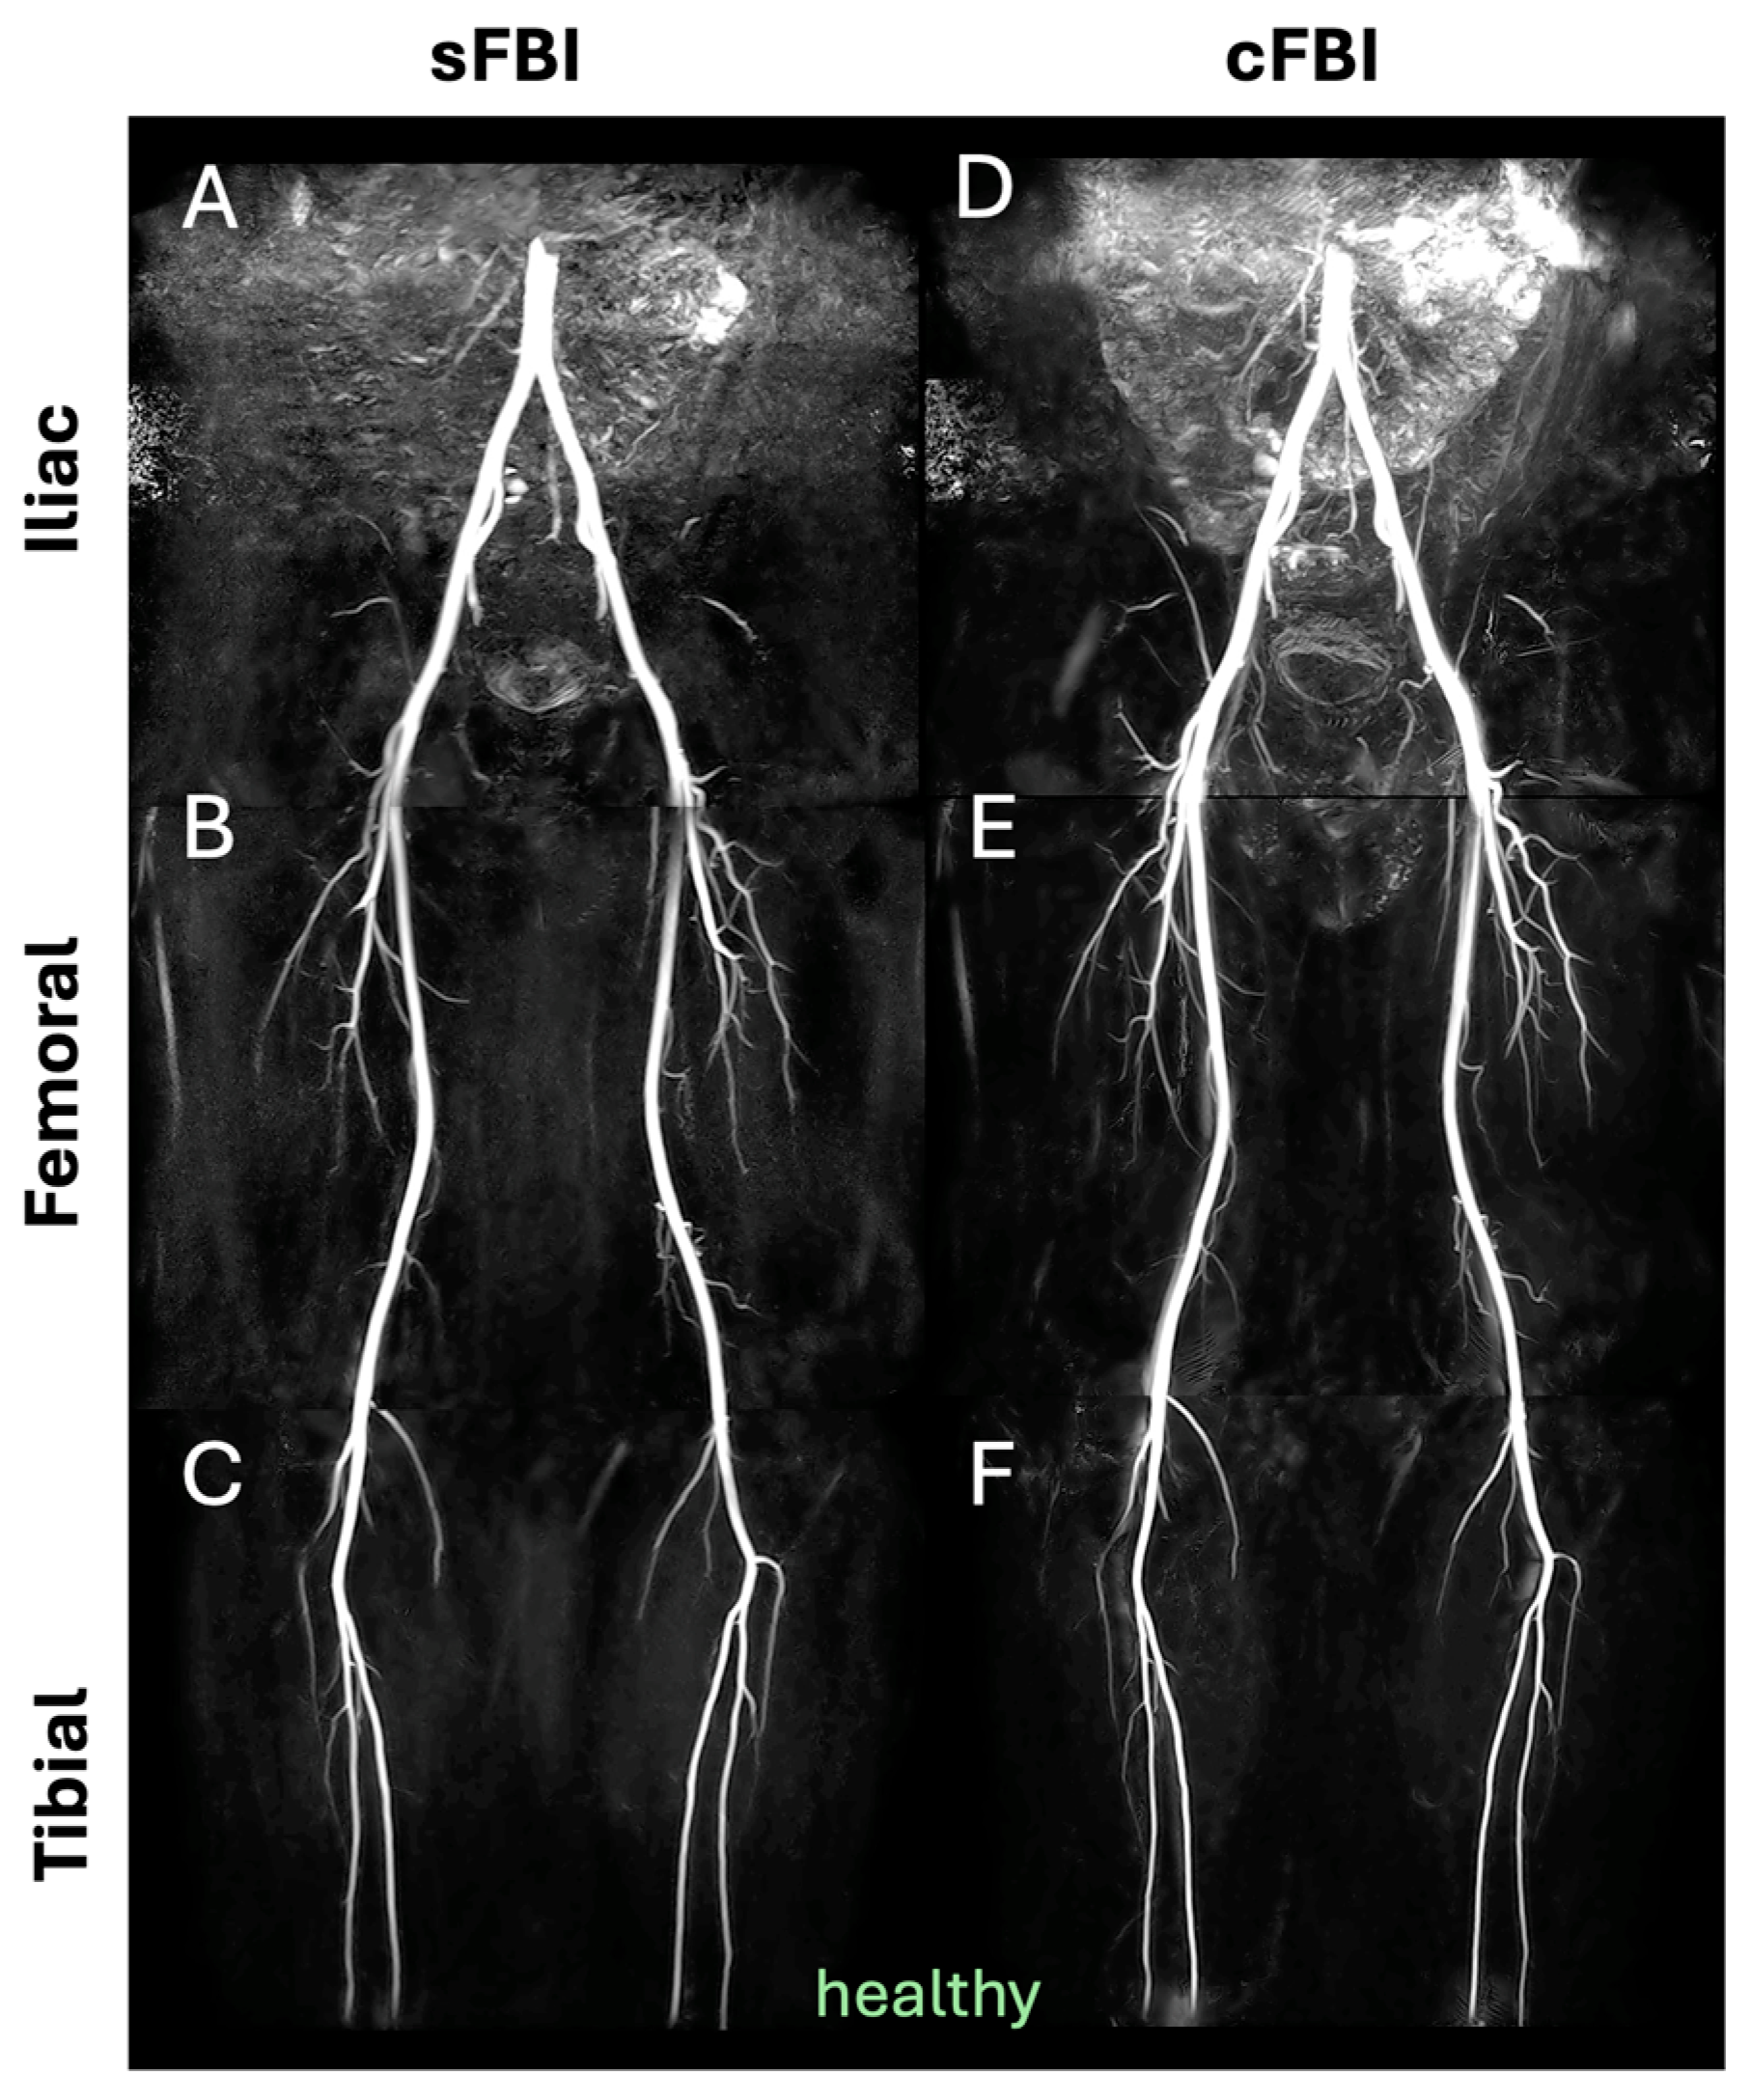

- Malis, V.; Vucevic, D.; Bae, W.C.; Yamamoto, A.; Kassai, Y.; Lane, J.; Hsiao, A.; Nakamura, K.; Miyazaki, M. Fast Non-contrast MR Angiography Using a Zigzag Centric k(y) − k(z) k-space Trajectory and Exponential Refocusing Flip Angles with Restoration of Longitudinal Magnetization. Magn. Reson. Med. Sci. 2025, 24, mp-2023. [Google Scholar] [CrossRef] [PubMed]

- Bae, W.C.; Hahn, L.; Malis, V.; Mesa, A.; Vucevic, D.; Miyazaki, M. Peripheral Non-Contrast MR Angiography Using FBI: Scan Time and T2 Blurring Reduction with 2D Parallel Imaging. J. Imaging 2024, 10, 223. [Google Scholar] [CrossRef] [PubMed]